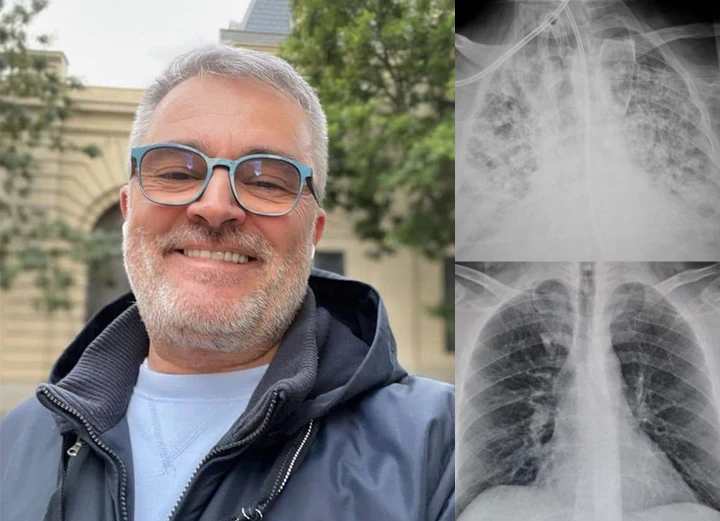

Hear From 150,000+ Satisfied Customers Who Cleared Their Lungs with Timilk® HerbaAir

“Living in a polluted city, I battled constant wheezing and exhaustion for years. Medications helped but made me feel drained. With Timilk® HerbaAir nasal inhalation, I felt my airways open up within 2 minutes of first use! My cough disappeared within two weeks, and breathing became much smoother. The instant relief is incredible.” — Linda M., Age 52,

“After smoking for over a decade, climbing stairs left me breathless. I tried various remedies with no improvement until Timilk® HerbaAir nasal inhalation. I couldn’t believe how quickly I felt relief! After one week, I could walk up five floors without gasping. My constant cough vanished completely.” — Bianca F., Age 47,

“With emphysema for ten years, every morning was a struggle with tight chest and constant mucus. Mullein teas helped a little, but Timilk® HerbaAir nasal inhalation gave me immediate soothing relief from the very first use. Within two weeks, I could walk my dog again without stopping.” — Karen S., Age 68,